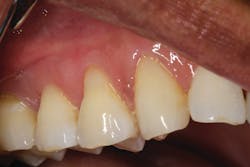

From the one- and one-and-a-half year postoperative images, we can analyze the longevity performance of the restorations. The restorations have proven to be color-stable and retain their polish and structural integrity (figures 5 and 6).References